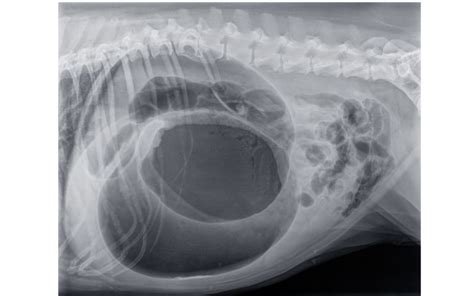

Pri výbere chovných zvierat sú potrebné určité kritériá na vyhotovenie röntgenových snímok a ich hodnotenie. U niektorých plemien, v niektorých krajinách alebo pri odborných posudkoch, je potrebný ďalší röntgen s roztiahnutými stehnami a nadvihnutými členkami (tzv. „žabí snímok“), pretože zmeny okraja kĺbovej jamky a stehenných kostí sú tak lepšie viditeľné.

- Obrazové metódy: Rentgen, ultrazvuk alebo magnetická rezonancia na odhalenie problémov s kosťami, kĺbmi a mäkkými tkanivami.

- Genetické testovanie: U plemien s predispozíciou na dyspláziu je vhodné pred zaradením do chovu vykonať röntgenologické vyšetrenie.